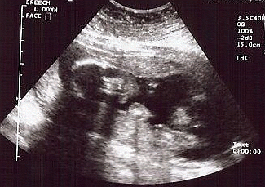

Second Ultrasound